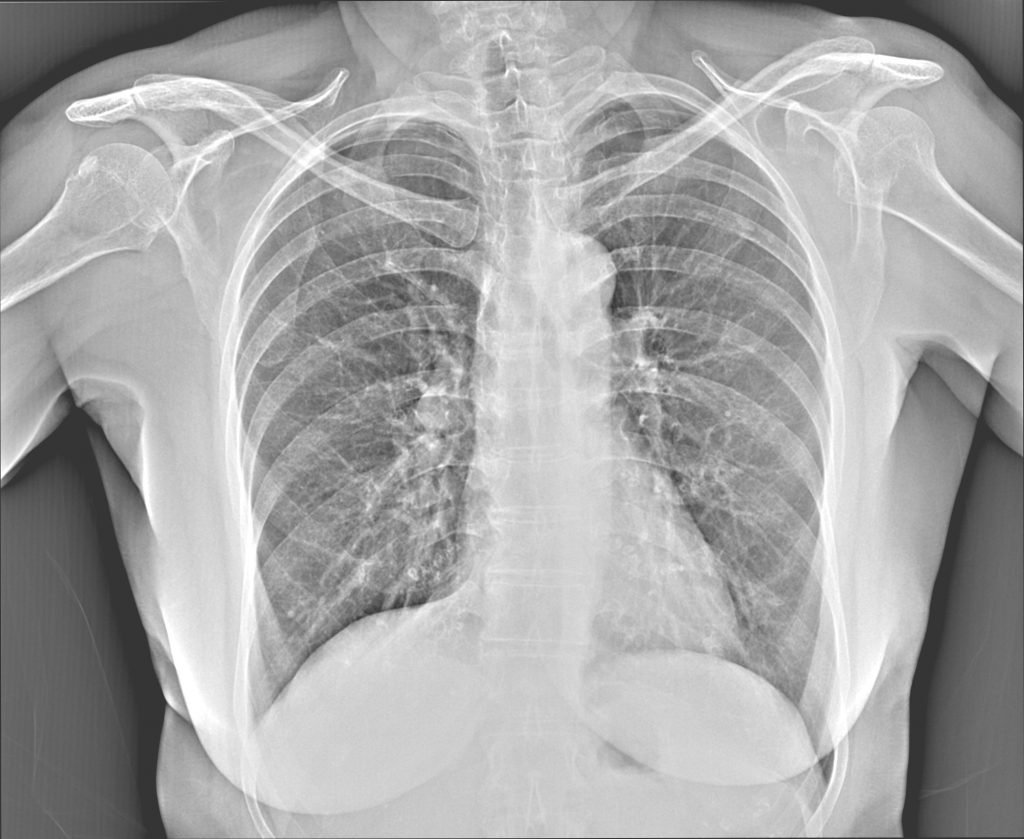

- Fast and accurate point-of care screening of Chest X-ray abnormalities

- Proprietary deep learning algorithm based on more than 500,000 of carefully annotated X-ray images provides high image reading accuracy